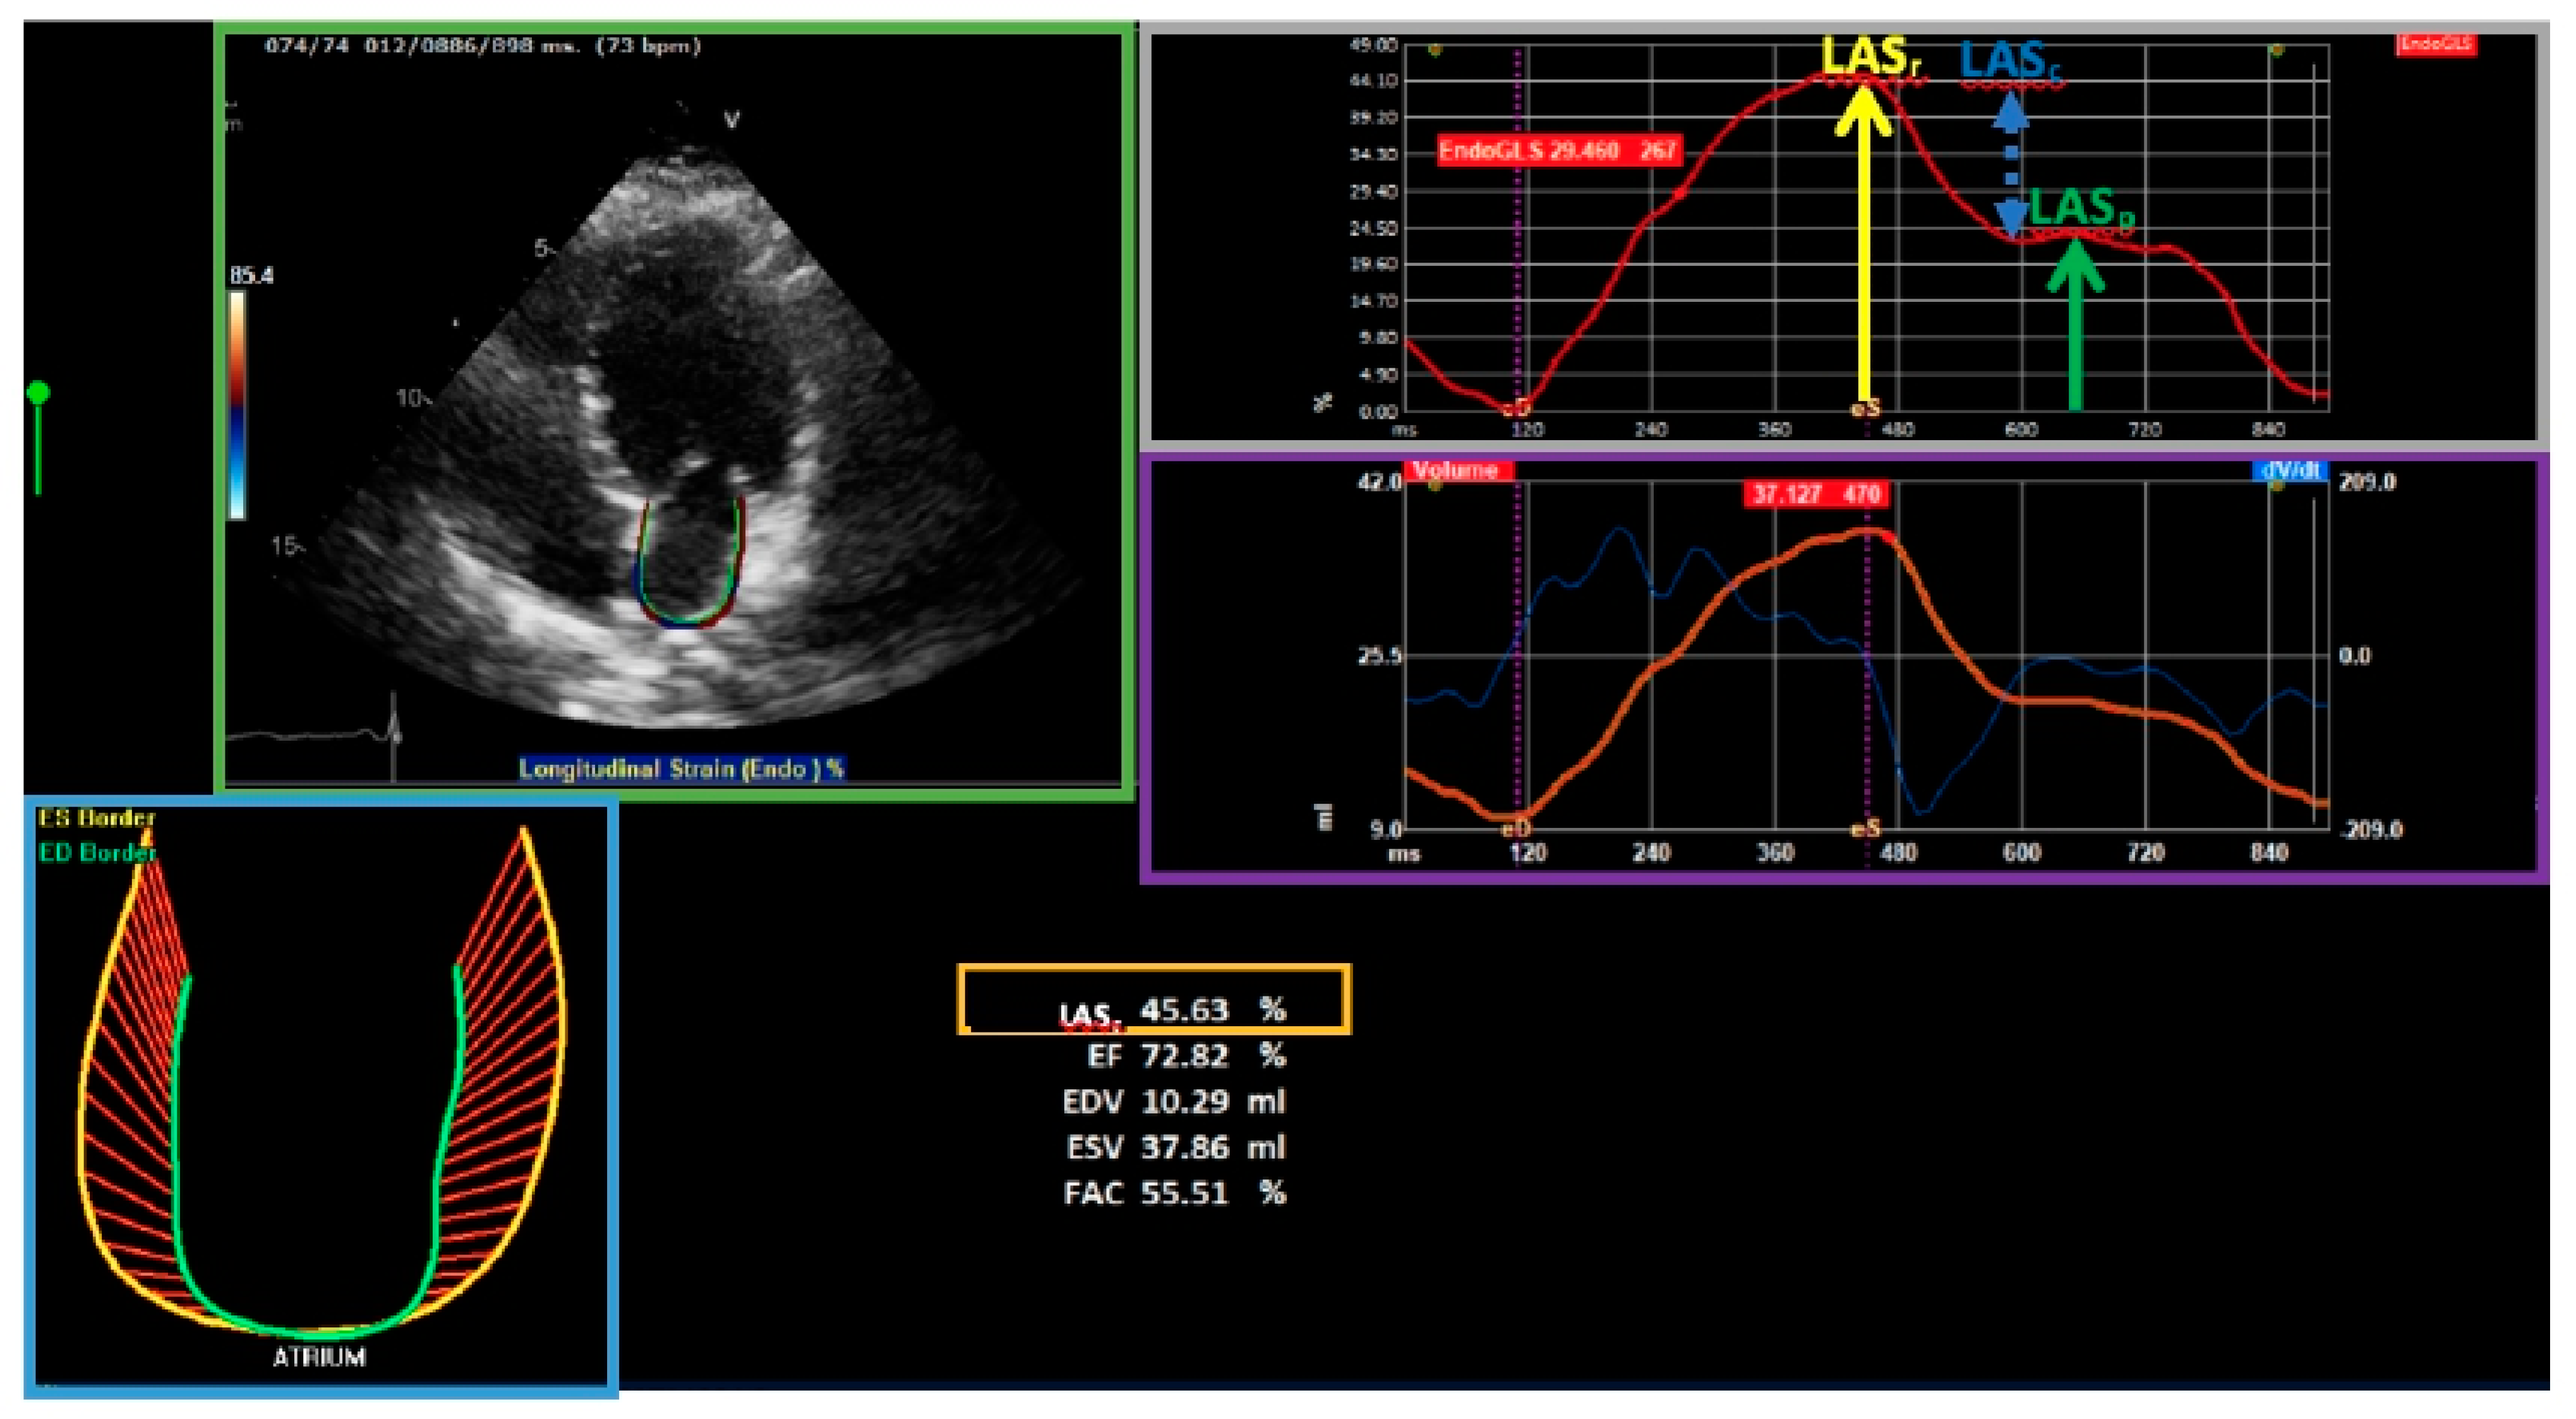

6. Left Atrial Strain